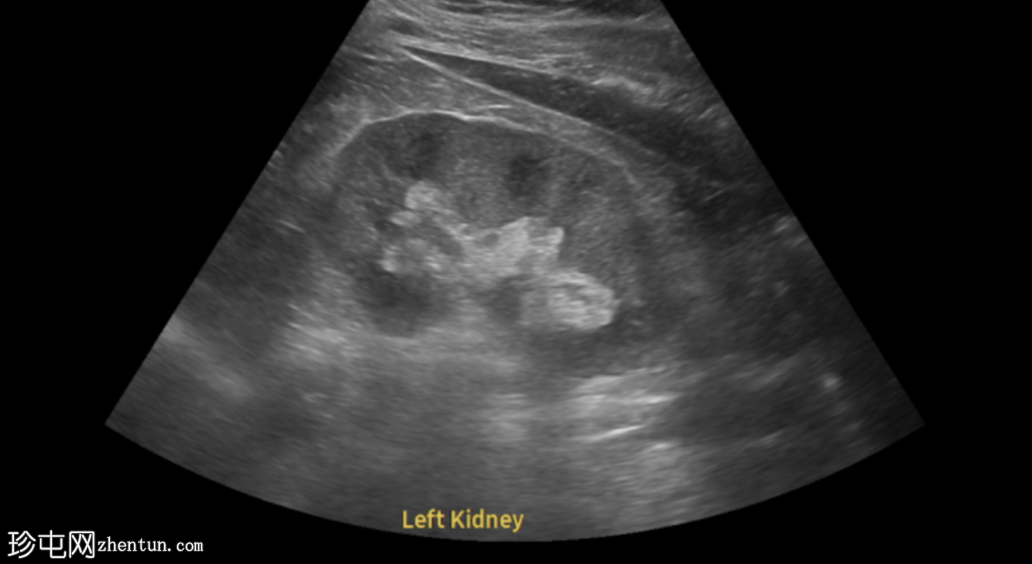

膀胱输尿管连接部结石

左侧腰痛伴血尿。

年龄:45岁

性别:男

超声

检查

超声显示左侧轻度肾积水,由膀胱输尿管连接处一枚7毫米的远端输尿管结石阻塞所致,输尿管射流正常。

肾积水并非总是由输尿管结石引起。肾盂和肾盏扩张的程度与结石大小并不一定相关。

较小的结石有时可导致中度上游扩张,而较大的结石可能仅引起轻微的充盈感,这取决于患者的引流和水合状态。